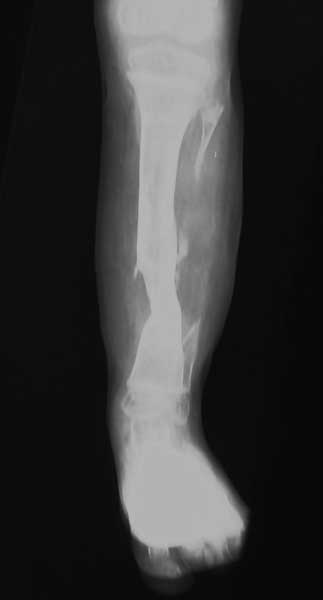

На основании литературных данных, наиболее эфективный метод лечения данной патологии является пересадка малоберцовой кости на сосудистой ножке и метод Илизарова.

Хочу поделиться с вами опытом недавно пролеченного мною мальчика пяти лет с врожденным псевдартрозом. ‚ вначале ему была пересажена малоберцовая кость. Операцию проводили с пластическими хирургами. Шесть месяцев спустя малоберцовка приросла, и мальчик начал ходить в специальном бандаже. —через некоторое время вследствие неаккуратности родителей (кто-то сел на ногу ребенка) произошел перелом на уровне стыка. Попытка срастить, наложив аппарат, была неудачной. Поэтому было принято решение удалить пересаженную малоберцовую кость и заместить дефект за счет верхней кортикотомии. Срок лечения один год. Был достигнут положительный результат. Спустя полтора года повторного перелома не наблюдалось.